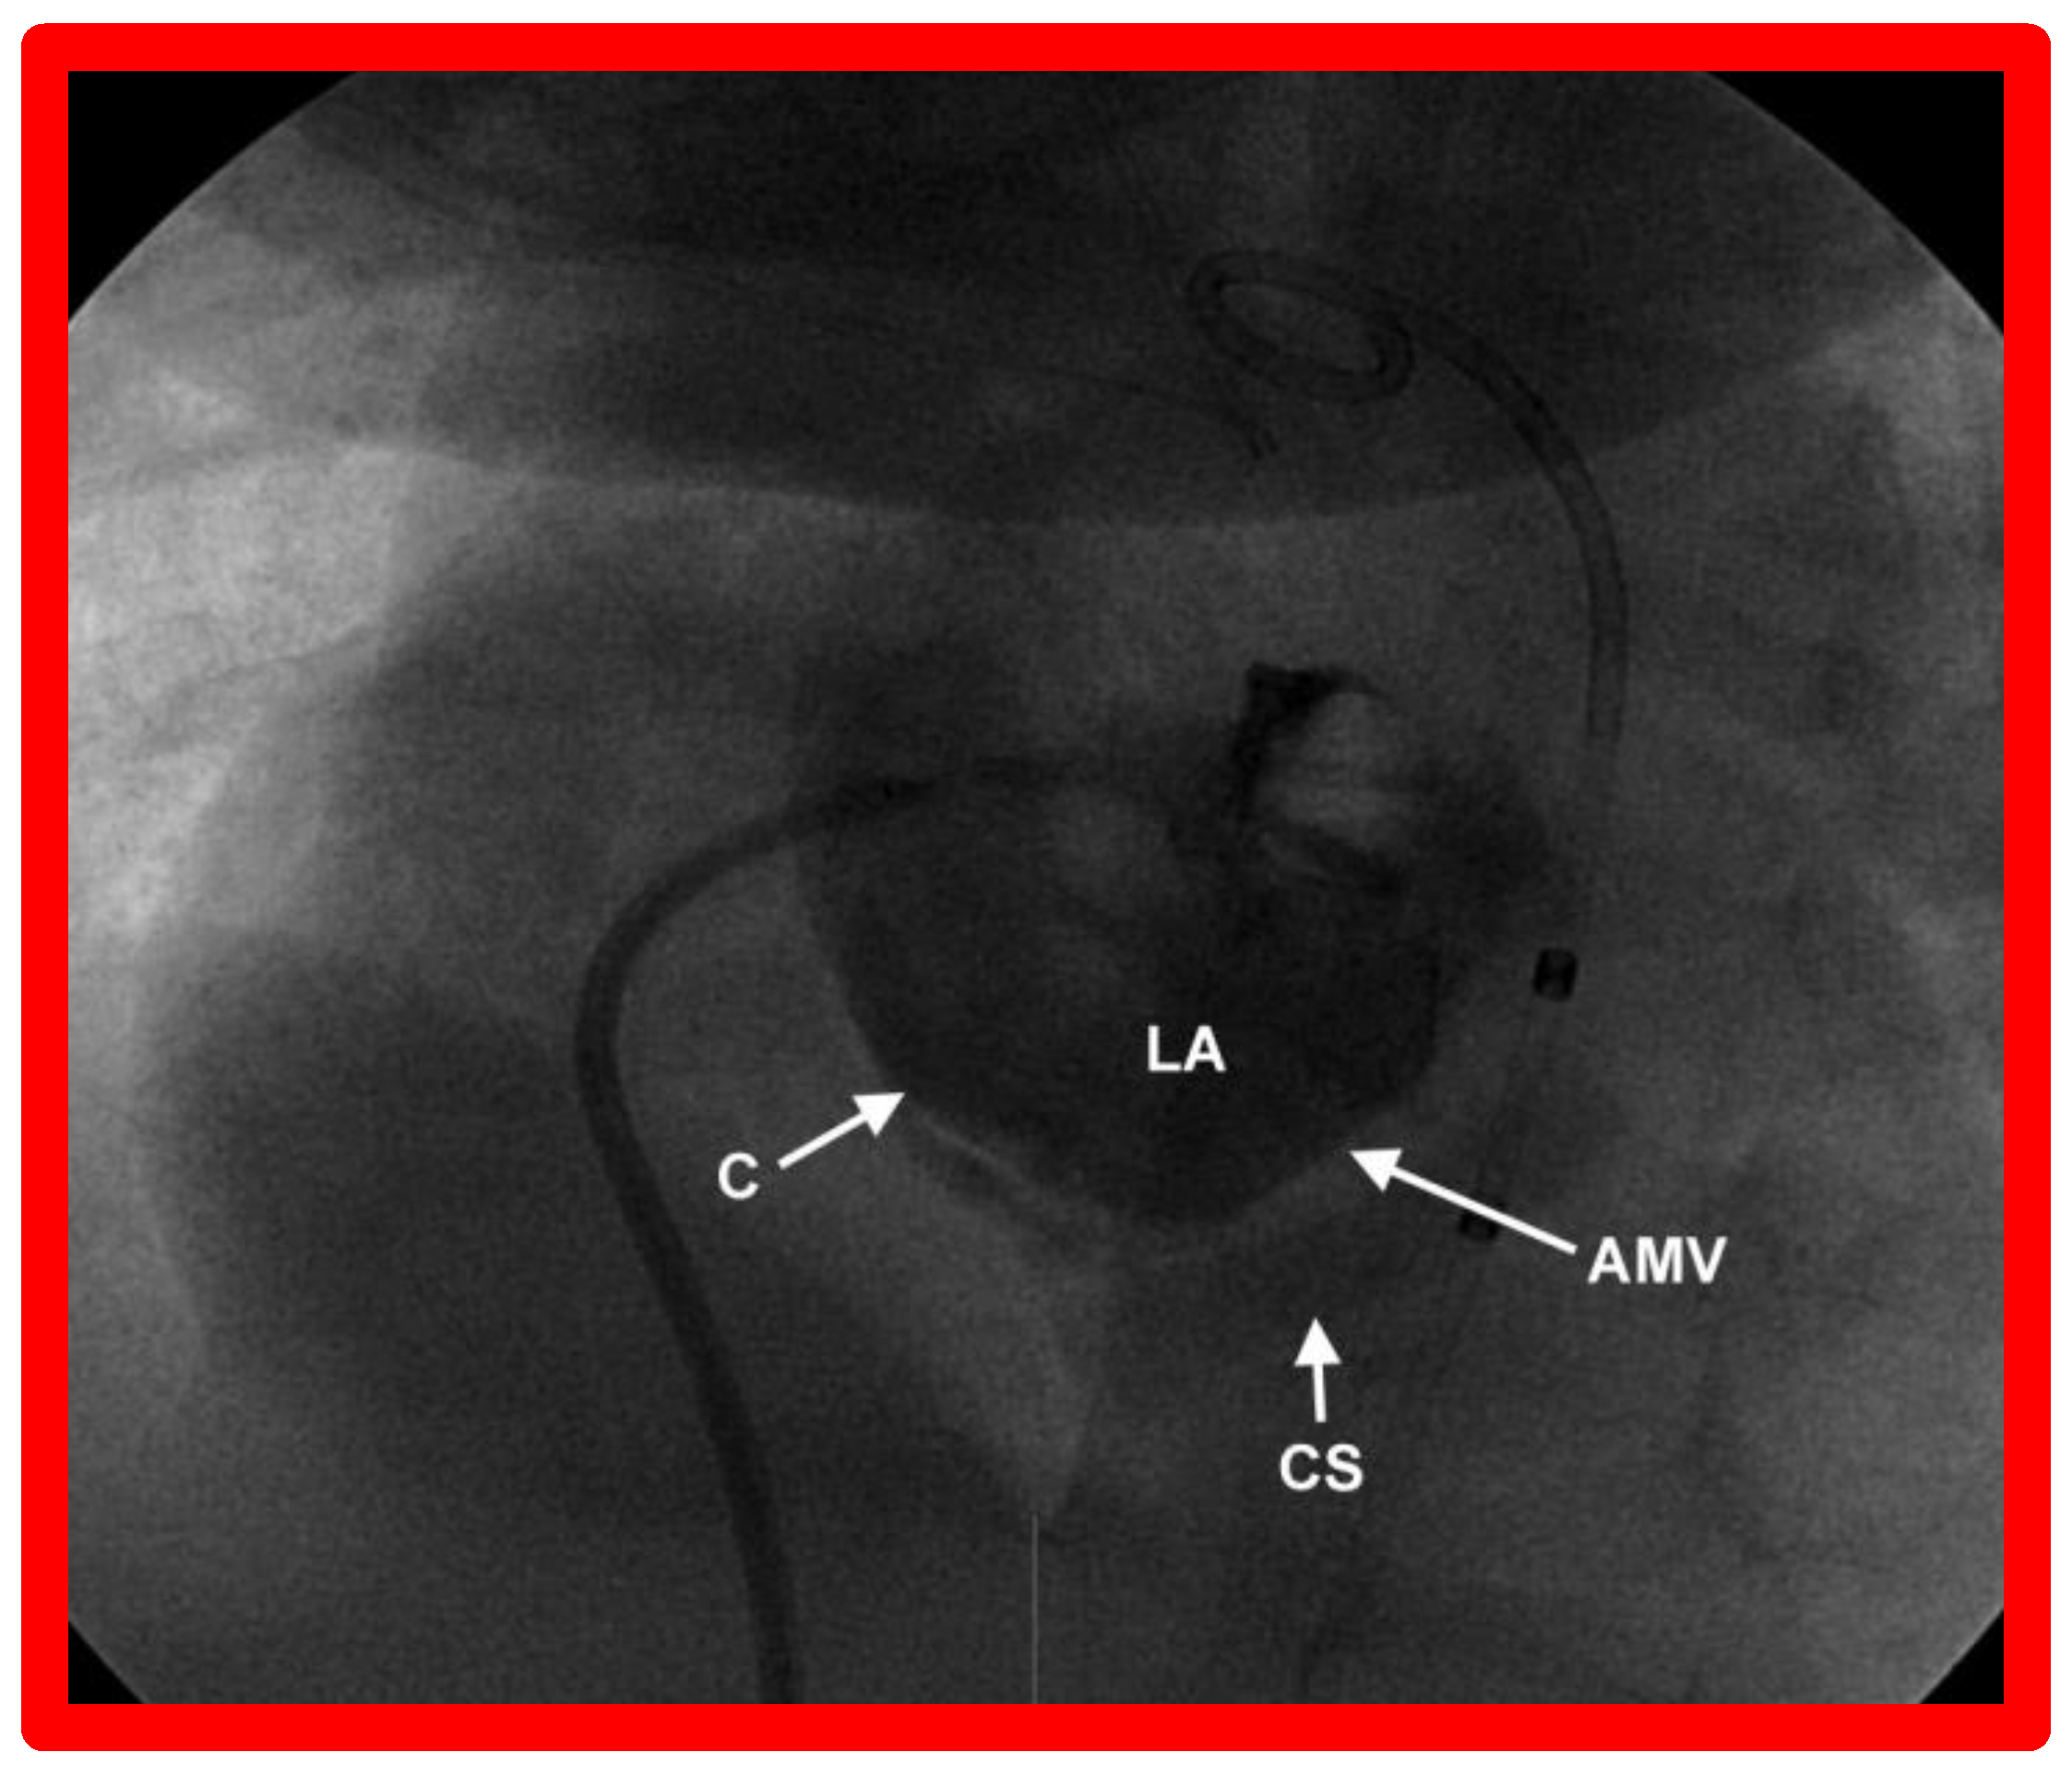

10.1.1. Inter-Atrial Obstruction